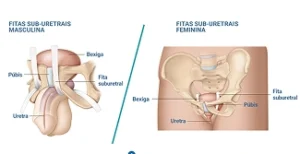

Tratamento da perda urinária e reconstruções pélvicas masculinas e femininas, com técnicas robóticas e minimamente invasivas.